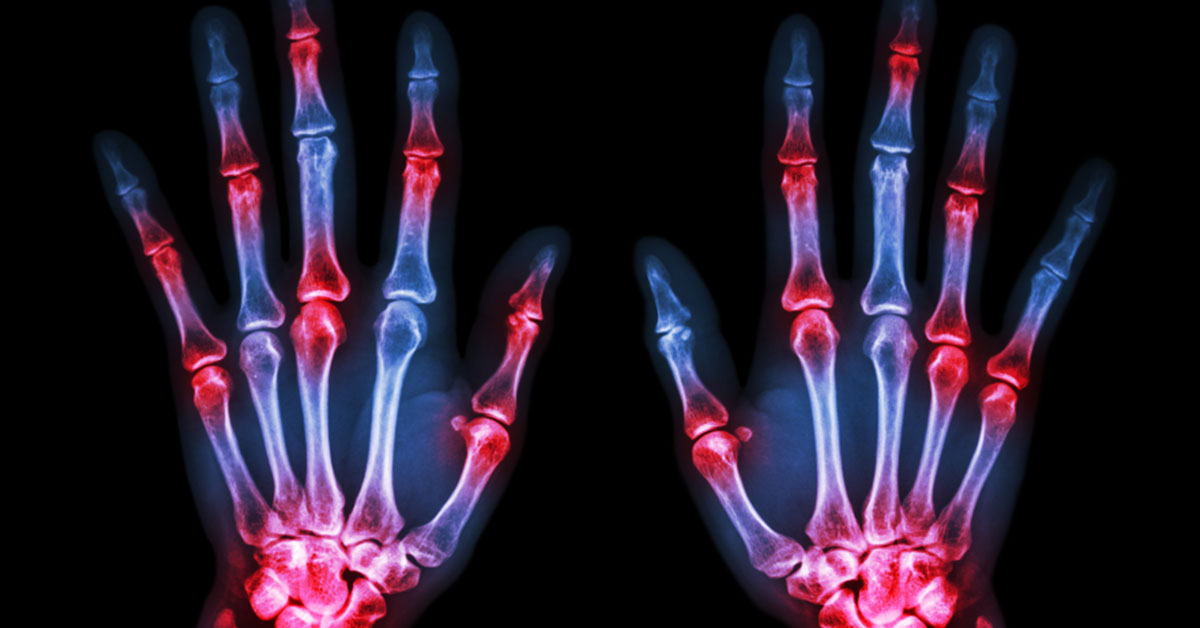

Acute arthritis refers to the sudden onset of joint inflammation. While many cases of acute arthritis can be managed with outpatient care, there are situations in which acute arthritis warrants immediate medical attention such as with septic arthritis, gout, and symptoms resulting from a drug reaction.

There are different types of arthritis, most of them affect the joints and body with pain and stiffness. It can be difficult to know if you have arthritis; however, there …

How to Identify Arthritis Symptoms Worthy of an ER Visit Arthritis is a common malady. Nearly 50 million adults in the United States suffer from arthritis. However, do you know …